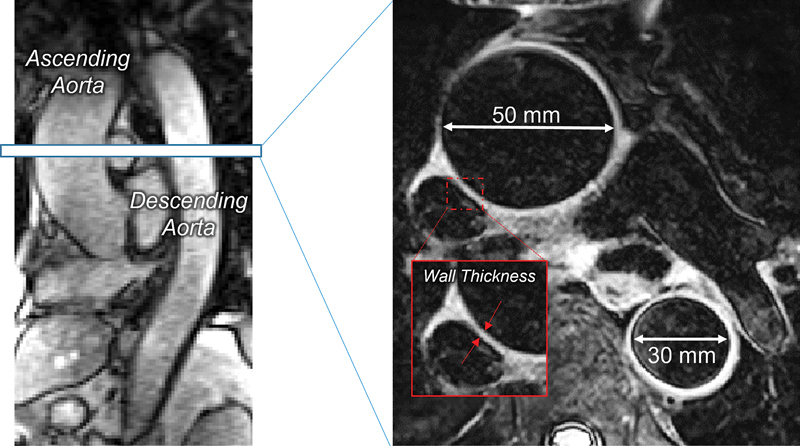

Individuals with ascending thoracic aortic aneurysm (ATAA) are recommended to avoid intense exercise for fear of marked increases in aortic wall stress (AWS). However, no study has measured AWS during exercise. The aim of this case series was to examine AWS during "light-to-moderate" aerobic exercise in individuals with ATAA and healthy control (CON) participants.Three clinically stable patients with ATAA (2 male, mean age: 74 ± 1 years) and 3 CON (2 male, mean age: 69 ± 7 years) were studied on 2 separate days. Day 1: a maximal cardiopulmonary exercise test was performed to measure peak aerobic power (VO2peak), maximal heart rate, and blood pressure (BP). Day 2: cardiac and aortic magnetic resonance imaging were performed at rest and during submaximal (3-5 metabolic equivalents) "stepper" exercise during which cardiac output (Qc), aorta diameters, wall thickness, and BP were measured. Circumferential ascending and descending AWS were calculated in accord with LaPlace Law, whereas aorta mechanical efficiency was derived as the AWS/Qc slope.Patients with ATAA demonstrated lower median VO2peak (18.2 vs. 24.1 mL/kg/min). During exercise, the absolute ascending (ATAA: 257 vs. CON: 269 kPa) and descending AWS increased (ATAA: 224 vs. CON: 207 kPa), and ∆AWS during exercise was similar between ATAA and CON (Ascending, ATAA: 79 vs. CON: 62 kPa; Descending, ATAA: 64 vs. CON: 55 kPa). During exercise, ascending and descending AWS were 76 to 83% below ATAA rupture thresholds (i.e., 800-1,200 kPa) in all patients. Finally, exercise Qc was 17% lower and the ascending AWS/Qc slope was 30% higher in ATAA (16 kPa/L/min) versus CON (12 kPa/L/min).Our findings demonstrate "light-to-moderate" aerobic exercise produces similar AWS responses between ATAA and CON and is well below aneurysmal rupture thresholds. The higher AWS/Qc slope in ATAA suggests decreased aortic mechanical efficiency and may be a useful measure for exercise prescription for these patients.